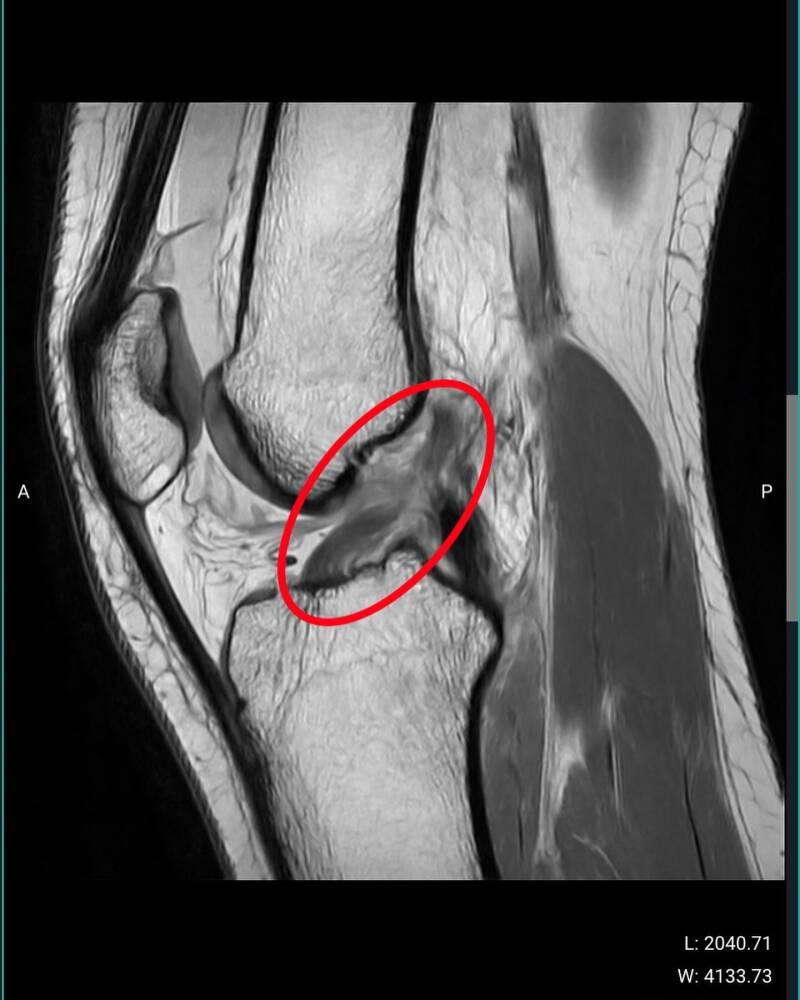

Van 7 september tot en met 13 september 2024 kon je me vinden op het WK Skateboarding street in Rome.  Ik was er helemaal klaar voor en ik had een run die veel punten zou opleveren. Jammer genoeg ging het niet zoals gehoopt. Tijdens de tweede practice dag ben ik verkeerd neergekomen waardoor ik mijn knie zwaar geblesseerd heb. Ik kon niet meer meedoen aan het WK, wat voor mij een grote teleurstelling was.

Na de World Skate Games in Italië gingen we terug naar het thuisfront. Ik had een spoedafspraak voor en MRI-scan te maken van mijn knie. De scan gaf een minder leuk resultaat dan gehoopt want ik had mijn voorste kruisband en meniscus gescheurd.

Op 25 september 2024 werd ik geopereerd. Alles is goed gegaan! Ik moest direct kinesitherapie volgen om te leren strekken en buigen. Het zal een lange revalidatie worden, maar ik geef niet op! #dreambigdaretofall